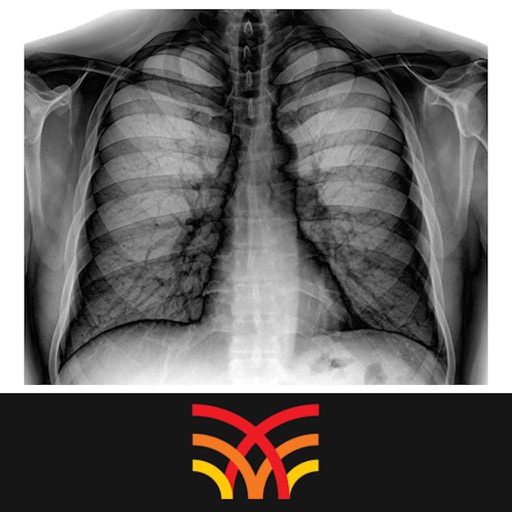

The reading and interpretation of radiographs is a skill that depends very much on practice and experience. Not only does it take time to know the difference between the normal and the pathological, but it also requires some training and practice to be able to define normal radiographic anatomy. Your skills in radiographic interpretation may be enhanced if you adopt a systematic approach in looking at radiographs of patients in the context of their clinical presentations. We have developed a set of radiograph-interpretation schemes that may help you attain the skills required to study and make clinical decisions based on your understanding of a patient's radiographic investigations.